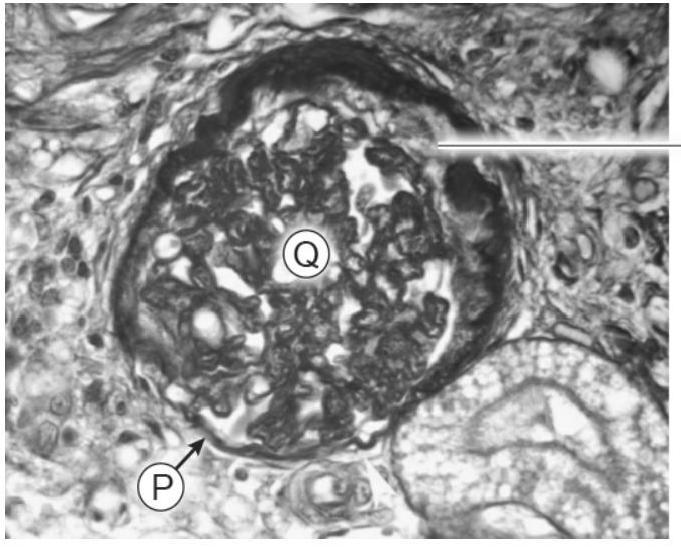

Bij chronisch nierfalen is de nierfunctie sterk verminderd, waardoor afvalstoffen zich ophopen in het bloed. Katten met chronisch nierfalen drinken daardoor veel. |